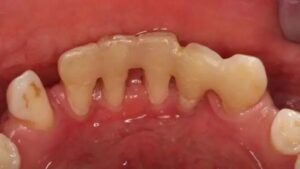

- Severely broken teeth: If only the root remains and it’s healthy (not inflamed), dentists can often rebuild the tooth using a post and crown—even if more than half the original tooth is gone.

Only when a tooth has no remaining structure, is beyond repair, or poses a risk to surrounding teeth should extraction be considered. Replacement options like implants or dentures should be reserved for truly missing teeth—not as a first solution.